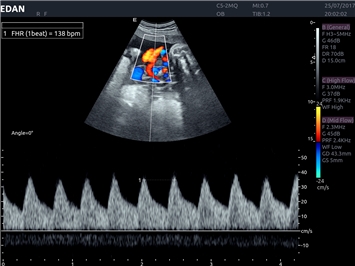

EDAN Acclarix LX4 представляет собой инновационную ультразвуковую систему, построенную на усовершенствованной платформе Acclarix. Сочетание высокого качества визуализации с интеллектуальным рабочим процессом делает эту систему оптимальным выбором для клиник, ценящих эффективность и экономичность.

Передовые технологии визуализации:

Инновационные функции обработки изображений:

• Запатентованная технология адаптивной визуализации тканей

• Функция eSRI для подавления зернистости изображения

• 3D/4D-визуализация с автоматическим редактированием объема (eFace)

• Панорамная визуализация

• Тканевая допплеровская визуализация (TDI)

• Специализированная технология визуализации иглы

Цветовой допплер:

Да

Импульсно-волновой допплер: